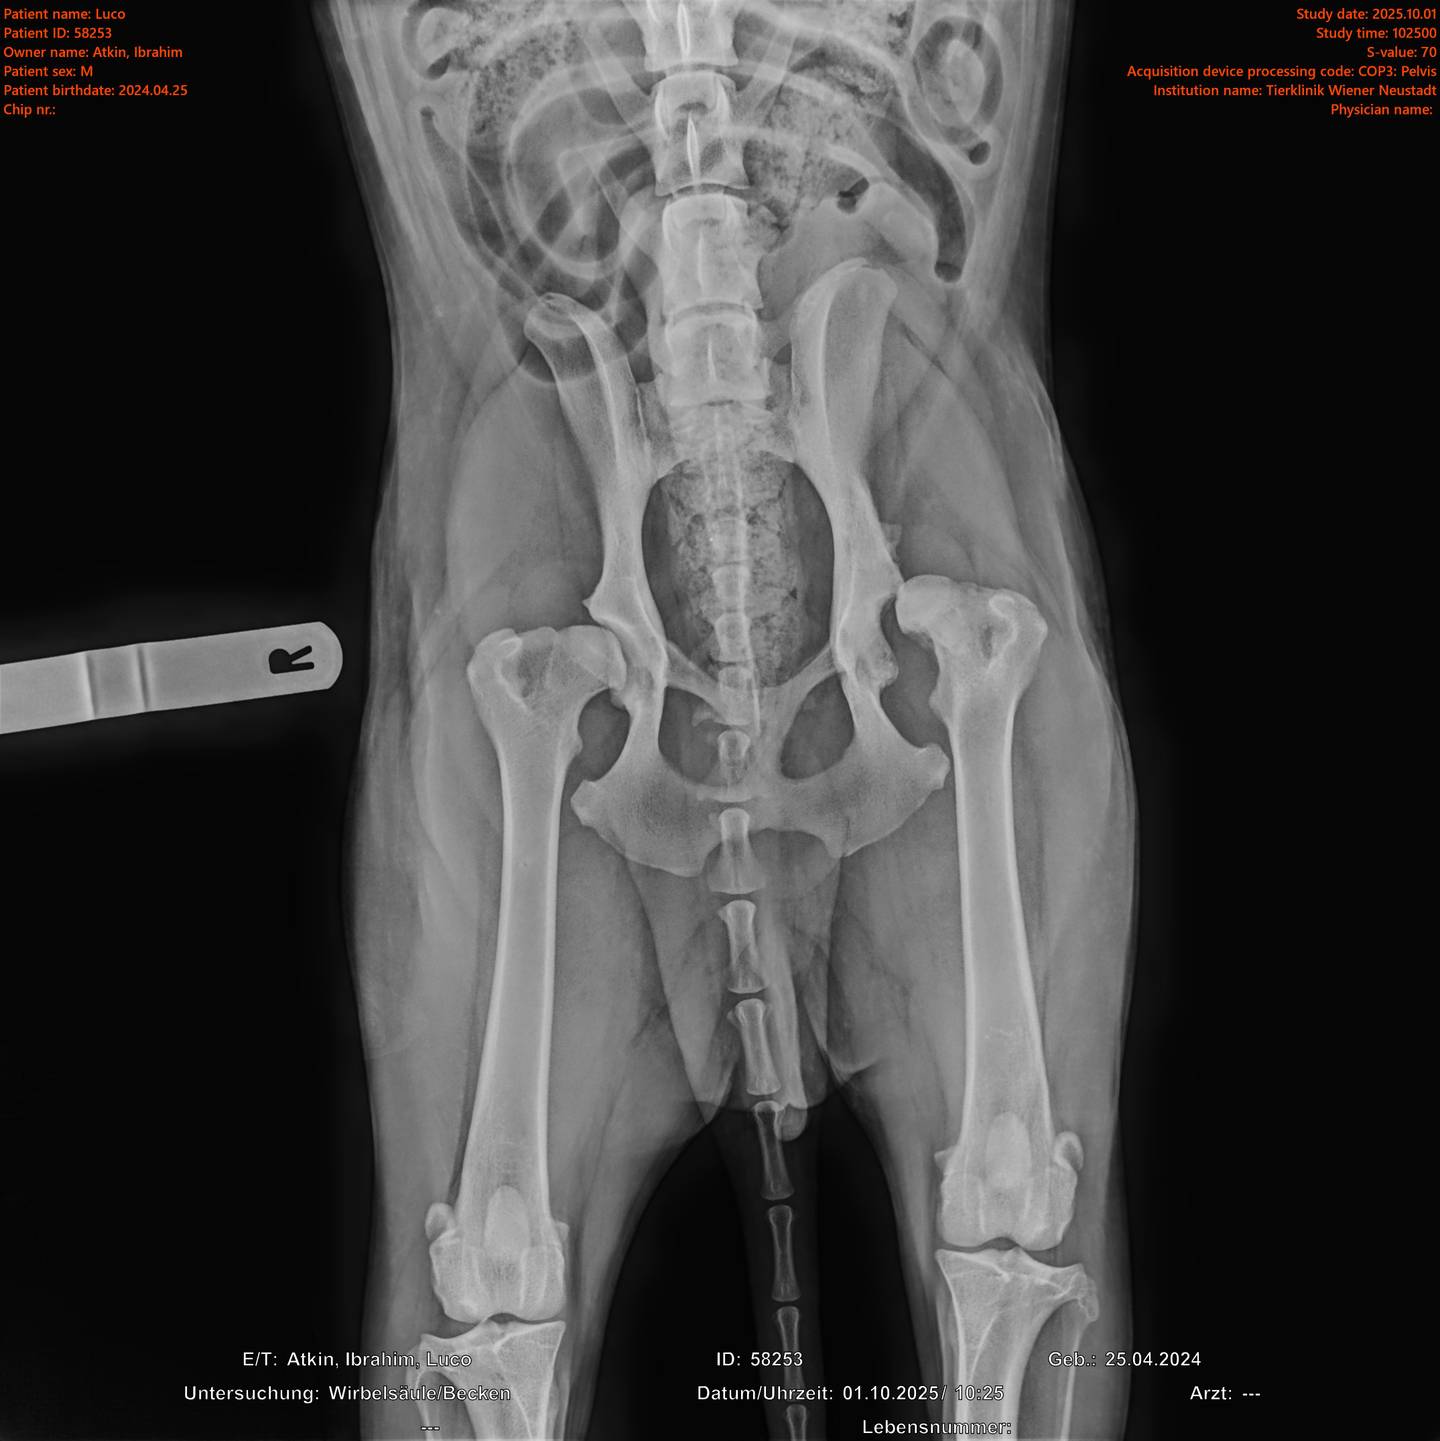

Unser Spezialisten-Team sowie modernste technische Geräte ermöglichen das Angebot eines breiten Spektrums professioneller und komplexer Leistungen. Wir bringen unser medizinisches Wissen in allen Fachbereichen laufend auf den neuesten Stand. Eine strategische Vorgehensweise zur Abklärung der Erkrankung mit dem Ziel, klare Diagnosen zu stellen, hat für uns oberste Priorität. Unsere Tierärzte sind spezialisiert auf Kleintiere und Heimtiere. Zu diesen gehören Hund, Katze, Kaninchen, Meerschweinchen, Frettchen, Hamster, Maus, Ratte und Chinchilla. Wir möchten ausdrücklich darauf hinweisen, dass wir für die Behandlung anderer Tierarten nicht entsprechend ausgestattet sind und daher nicht annehmen. Dazu gehören unter anderem auch Vögel und Exoten.

Tierklinik Wiener Neustadt